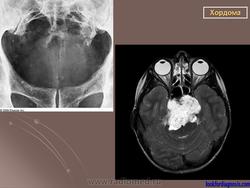

Хордома развивается из персистирующих остатков хорды. Преимущественная локализация хордомы - это область сфеноокципитального сочленения и крестцово-копчиковый отдел позвоночника. Сведения о частоте отдельных форм хордомы весьма разноречивы.

Jaffe приводит следующие данные: кранильные хордомы - в 35%, вертебральные - в 10%, каудальные - 55%. По данным С. А. Рейнберга, 60% всех хордом определяется в области крестца, в частности, 40% У основания копчика и только небольшой процент хордом локализуется в области основания черепа.

Рентгенологическая картина хордом характеризуется наличием очага деструкции, захватывающего ряд позвонков. Костный дефект представляется однородным, либо крупнокамерным за счет тонких костных полосок. Показаны боковые рентгенограммы крестца, на которых при хордоме определяется увеличение передне-заднего размера крестца за счет экспансивного роста опухоли. В отдельных случаях в опухоли прослеживаются небольшие костные включения, которые могут служить поводом для ошибочной диагностики тератом, особенно в детском возрасте. (В детском возрасте тератомы встречаются часто, их соотношение с хордомами, по данным М. В. Волкова, 60:2).